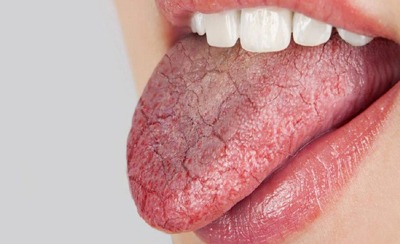

یک رژیم غذایی سرشار از قند در ترکیب با بهداشت نامناسب دهان و دندان به پوسیدگی دندان و فساد در خط لثه منجر می شود. آیا به طور مداوم با خشکی و چسبندگی دهان مواجه هستید؟ بیشتر مواقع، خشکی دهان به واسطه دلیلی ساده مانند کم آبی بدن یا شرایط آب و هوایی رخ می دهد. اما اگر بدون در …